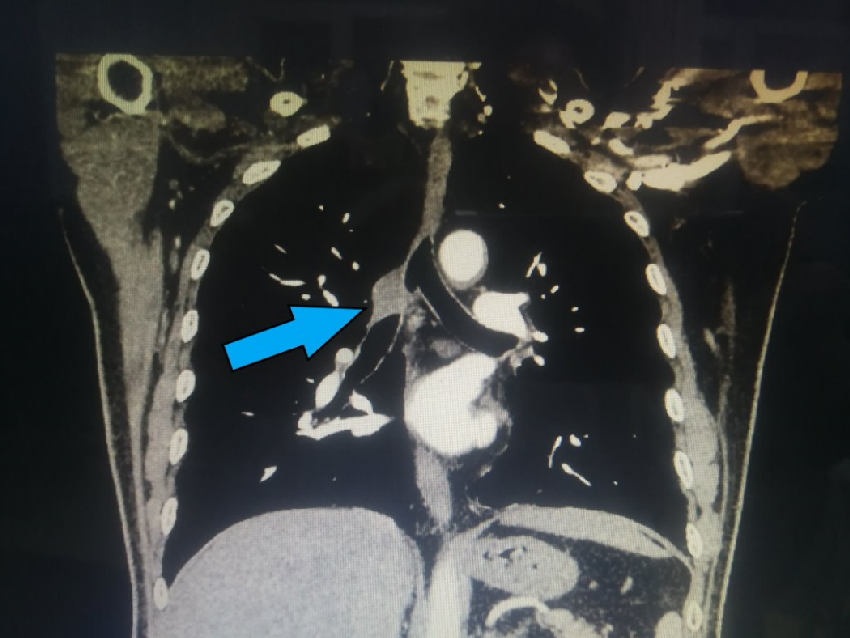

3月16日,辽宁省肿瘤医院副院长、胸外科刘宏旭主任、王伟主任及团队其他成员在麻醉科高浩然教授、手术室顾鑫和宋顺庆两位护士的配合下顺利完成一例非气管插管保留自主呼吸胸腔镜下袖式切除微创手术。随着年味逐渐散去,国内疫情形式逐渐明朗,医院就医的患者也逐渐的增多。在忙碌的工作中,我院胸外科刘宏旭教授团队始终坚持以患者生命健康为中心,在保证患者就医需求的基础上,一直紧跟着创新的步伐。3月16日完成的非气管插管保留自主呼吸胸腔镜下袖式切除微创手术,填补了我院乃至辽宁省在复杂中心型肺癌的微创手术区域的空白。       62岁的陈先生常年吸烟,1年前出现咳痰带血丝症状,当时未重视。近来出现呼吸困难,行胸部CT(见图1、2)检查提示右主支气管壁不规则增厚,可疑恶性;进一步行支气管镜(见图3)检查提示右肺上叶管口新生物,累及右主支气管开口及右肺二级隆突及中间干支气管,上界平隆突水平,下界距离中下叶开口约1cm,取病理提示鳞癌。  图1 图2 图3       面对这晴天霹雳,患者家属经过多方打听,了解到我们团队对于中心型肺癌的治疗有着丰富的经验并直接找到我们。经胸外科、胸内科、胸部放疗科、影像科和麻醉科共同会诊,专家们一致认为目前外科手术切除是最适合患者的治疗方案,但肿瘤位置高,单纯的支气管袖式切除不一定能达到完整切除的目的,很有可能需要隆突成形。考虑到手术当中气管吻合的难度及患者术后恢复,非气管插管麻醉方式比常规气管插管麻醉更具有优势。在保证肿瘤完整切除的前提下,本着对患者负责和对技术精益求精的心态,经充分的术前准备,于2021年3月16日成功行非气管插管保留自主呼吸胸腔镜下右肺上叶袖式切除、隆突成形、迷走神经部分切除重建、肺门纵隔淋巴结廓清术。(见图4、5、6、7)术中病理回报:气管上、下切缘净,这说明肿瘤切除彻底。       患者术后胸片见右侧余肺复张良好,气管镜见吻合口完整、通畅(见图8)。术后经过胡秀芬护士长领导的护理团队精心护理,给予患者快速康复和“无痛”优质护理,术后第1天下地活动,第3天拔除引流管,第4天恢复顺利出院。     图8       中心型肺癌病灶生长于肺脏根部,要想完整切除病灶,在多数情况下可能只有将单侧全肺切除,该手术方式无疑对患者造成了很大的伤害。支气管袖式切除术是将病灶连同被侵犯的支气管一同切除,再将正常的支气管两端切缘吻合。该手术方式是治疗中心型肺癌的标准术式之一,与单侧全肺切除比较,术后长期生存结果可与之相媲美,并更加有利于改善生活质量。非气管插管麻醉是术中使用不侵入气管的气道装置进行通气,保留患者自主呼吸,利用人工气胸达到单肺通气的效果。这种麻醉方式不仅能降低术后咳嗽等呼吸系统并发症,而且能缩短术后离床时间、禁食时间、住院时间及费用。胸腔镜手术技术凭借特有的优势(创伤小、手术视野好、术后恢复快)目前已被广泛应用,将胸腔镜下支气管袖式切除技术与非气管插管技术相结合,无疑可以进一步减少支气管袖式切除术的创伤,能最大限度地保护患者,更好的服务于患者。它的成功开展,标志着我院胸外科团队医疗水平达到了一个新高度。更重要的是,这种术式既避免了全肺切除术后治疗的困难,也最大程度上保留了患者的肺功能和最小限度下减少手术创伤,极大的改善中心型肺癌患者的生活质量。相信,辽宁省肿瘤医院胸外科将继续秉承“精诚•专业•仁爱 成就生命所托”的医院精神,不惧挑战,精益求精,砥砺前行,为更多患者提供更大的帮助。